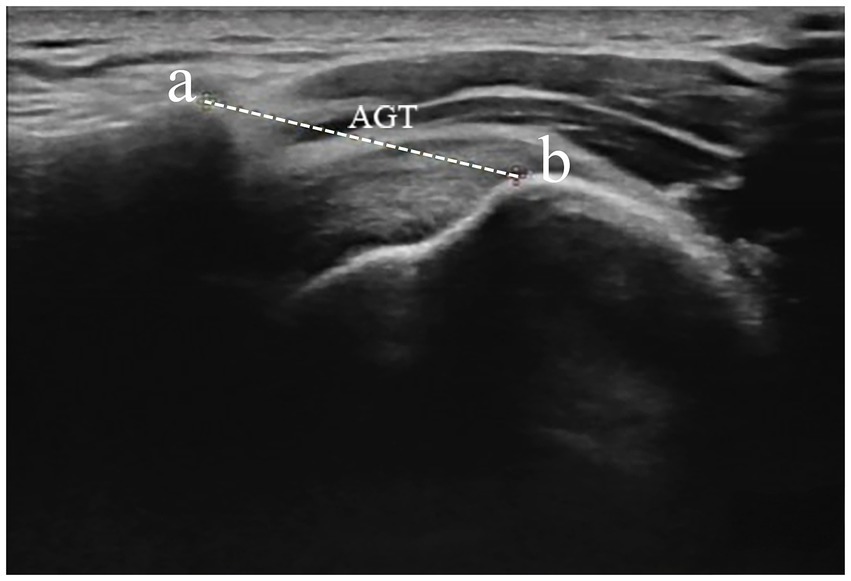

Figure 5

Measurement of AGT distance from the lateral border of the acromion and the nearest superior margin of the greater tuberosity. Dotted caliper represents AGT distance. AGT acromion–greater tuberosity. a—acromion, b—greater tuberosity.

In the evaluation of AGT during ultrasound procedures (RS80A, Samsung, Korea), the research included 22 healthy participants based on the informed consent of each participant. The participants’ posture required is consistent with the posture of radiographic measurement of AHD. The transducer was positioned at the anterior edge of the shoulder within the coronal plane (Figure 4). After the acromion and greater tuberosity of the humerus appeared on the screen, the image was captured, allowing for the measurement of the shortest distance between the acromion and the greater tuberosity (18) (Figure 5). Data from bilateral AGTs were documented, and the ratio of the bilateral distances was calculated (Left/Right). Two separate measurements were utilized to evaluate reliability. These procedures were performed by a single ultrasonologist.